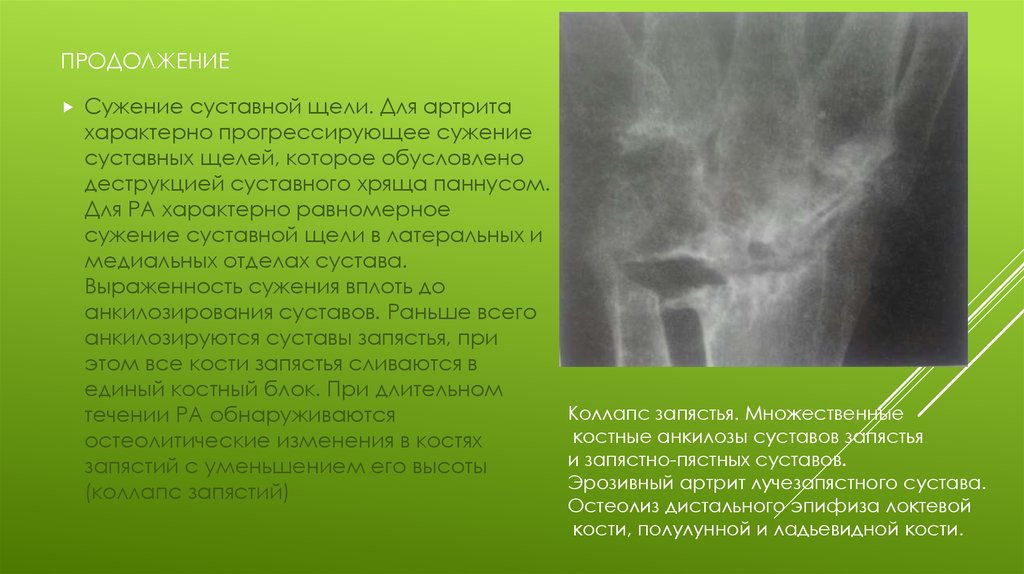

Ревматоидный артрит стопы: рентгеновские снимки и стадии заболевания

Раздел: Визуальный дайджест